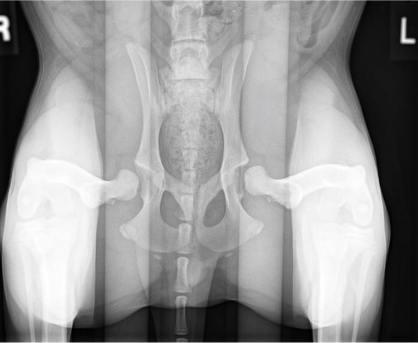

The most common radiographs made to evaluate dog hips are the traditional, “legs extended” view. These are also the type of radiographs that are reviewed by the Orthopedic Foundation for Animals (OFA) for grading. These radiographs are good, but imperfect. If these pelvic radiographs show a deformed hip, very loose hip, or an arthritic hip, one can confidently conclude that the dog hip is dysplastic. However, if the canine’s hips look good on these OFA radiographs, particularly in a puppy, there may still be laxity that just cannot be seen with these radiographs. That explains why OFA will not provide a grade on a dog’s hips prior to 2 years of age (unless the hips are obviously abnormal). This is due to the fact that these Orthopedic Foundation for Animals (OFA) style radiographs do not show hip looseness (laxity). As mentioned above, hip laxity is the first characteristic of hip dysplasia. Therefore, if the legs extended radiographs look very good, veterinary surgeons really want to know how lax (loose) the hips are. To know how loose the dog hips are, a veterinarian needs to take distraction radiographs.

Distraction radiographs, of which PennHIP radiographs are the most extensively studied and used, involve the physical distraction of the hips at the time of taking the X-ray to see how loose the dog hips are. From these PennHIP radiographs, the looseness is actually measured (called the distraction index; DI), not just subjectively estimated, and compared to the DI of many other dogs of only the same breed. With this information, a prediction is made as to the risk (ie probability) that your dog will develop hip osteoarthritis. These PennHIP distraction radiographs are most pertinent in assessing hips in young dogs that look good on the legs extended views. Knowing how loose those canine hips are, and the associated risk of developing osteoarthritis, can inform decisions on breeding that dog or on doing prophylactic surgeries to try and prevent the development of OA (see next).

OFA (left) and PennHIP (right) radiographs on the same canine patient. The hips look reasonable on the OFA images (left) but the extreme laxity is readily evident on the PennHIP radiographs.